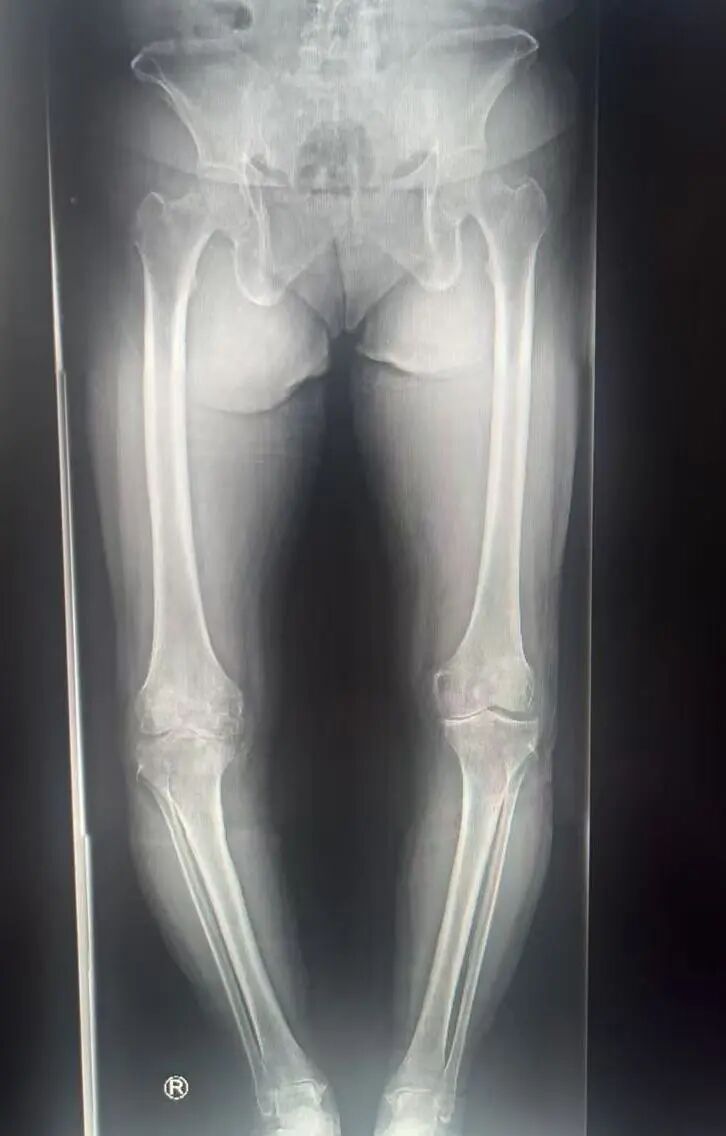

半年前,备受煎熬的苗阿姨找到关节与运动医学二科副主任王国华,看看能否彻底解决她的双膝疼痛问题。经过详细检查与诊断,苗阿姨被确诊为膝关节骨性关节炎,此时她的关节软骨已严重磨损、关节间隙狭窄,还伴随内翻畸形,保守治疗已无法有效缓解症状。王国华团队随即为她制定了个性化方案,成功实施了右膝人工关节置换术。

术前VS术后对比